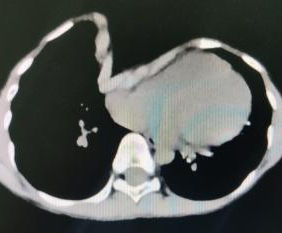

Preoperative Examination

A severe depression is present in the center of the chest wall, with the right edge of the depression forming a ridge-like protrusion. Meanwhile, the edges and bottom of the depression have developed acute angle deformities.